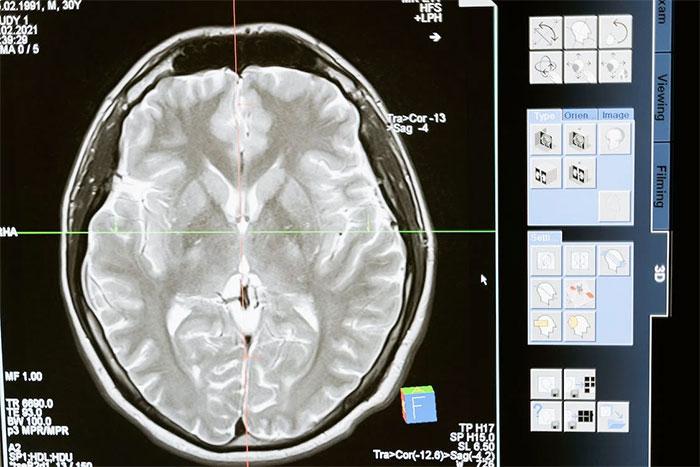

6. “Mozog v skutočnosti nevie dobre rozlišovať medzi predstavivosťou a realitou.“